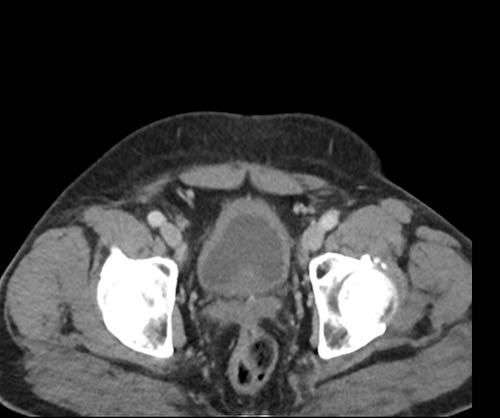

Ca lâm sàng 1

Cuộn qua các lát cắt.

Bạn có thể phát hiện tất cả các tổn thương cấy ghép phúc mạc không?

Bệnh nhân này đã được phẫu thuật và toàn bộ phúc mạc được ghi nhận phủ kín bởi các tổn thương u dạng kê.

Ca lâm sàng 2